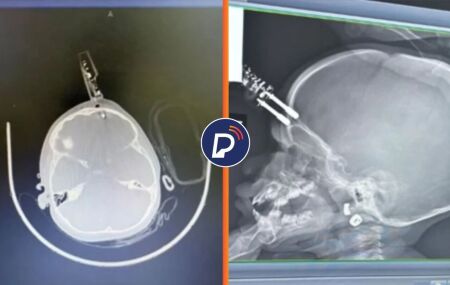

Imagens de raio-x que mostra carregador na testa da menina.

Menina de 1 ano cai da cama e fica com carregador cravado na testa

A principal hipótese é que a criança estaria com o objeto em mãos quando caiu da cama e atingiu a cabeça de uma forma que acabou resultando na perfuração.